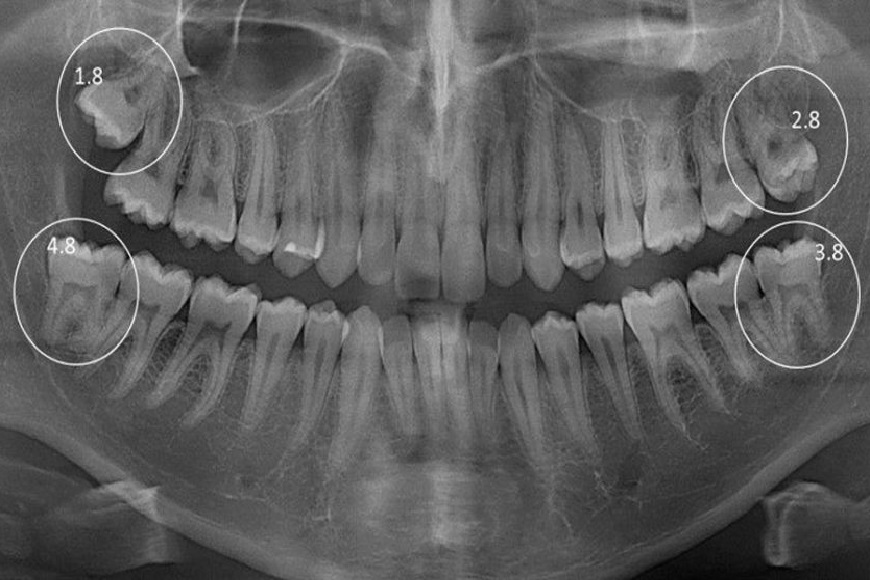

Una buona strategia, ampiamente condivisa oltre che piuttosto lungimirante può essere effettuare una ortopantomografia (radiografia panoramica delle arcate dentarie) intorno ai 14 anni. In questo modo si può monitorare la situazione e lo stadio di crescita dei denti del giudizio, valutando se vadano estratti verso i 16 anni o se si può aspettare ancora. Una volta analizzato accuratamente il caso si può eventualmente procedere all’estrazione degli ottavi in uno stadio di crescita in cui le radici non si sono ancora formate (germectomia).